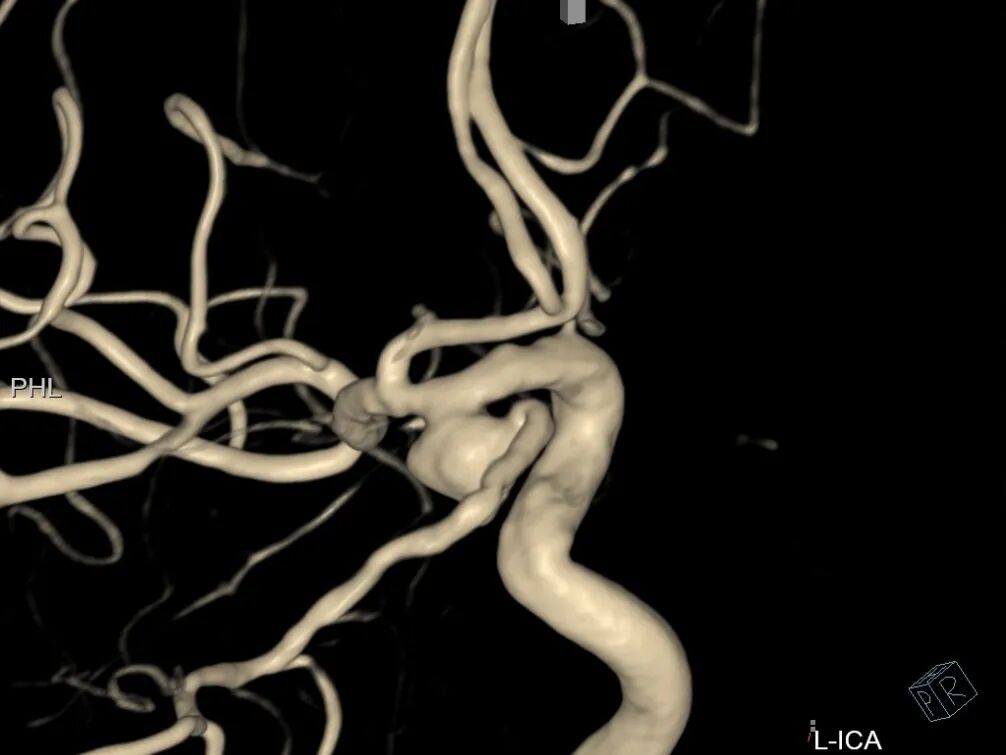

左侧颈内动脉3D造影可见动脉瘤位于后交通动脉起始处。

3D血管造影可见左侧后交通动脉瘤,大小约7.05×7.47mm,瘤颈3.68mm,考虑胚胎型大脑后动脉。